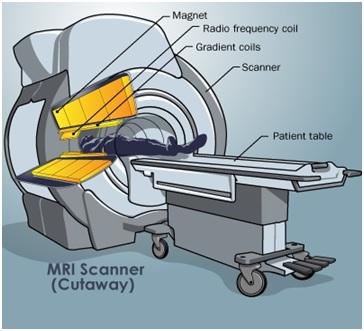

MRI stands for Magnetic Resonance Imaging. This technology relies on magnetism. It’s a more recent advancement compared to CT scans. MRI uses magnetism to create a 3D image of the body’s interior.

Similar to CT scanners, MRI machines have a moving platform. Patients lie down on this platform and are moved into a narrow cylinder. Magnets within the cylinder generate a strong magnetic field around the patient’s body. The cylinder is somewhat narrower compared to CT scanners. It’s crucial to remove all metallic objects from the body before an MRI scan. MRI scans can take around 30 minutes to complete.

Key components of an MRI scanner include: